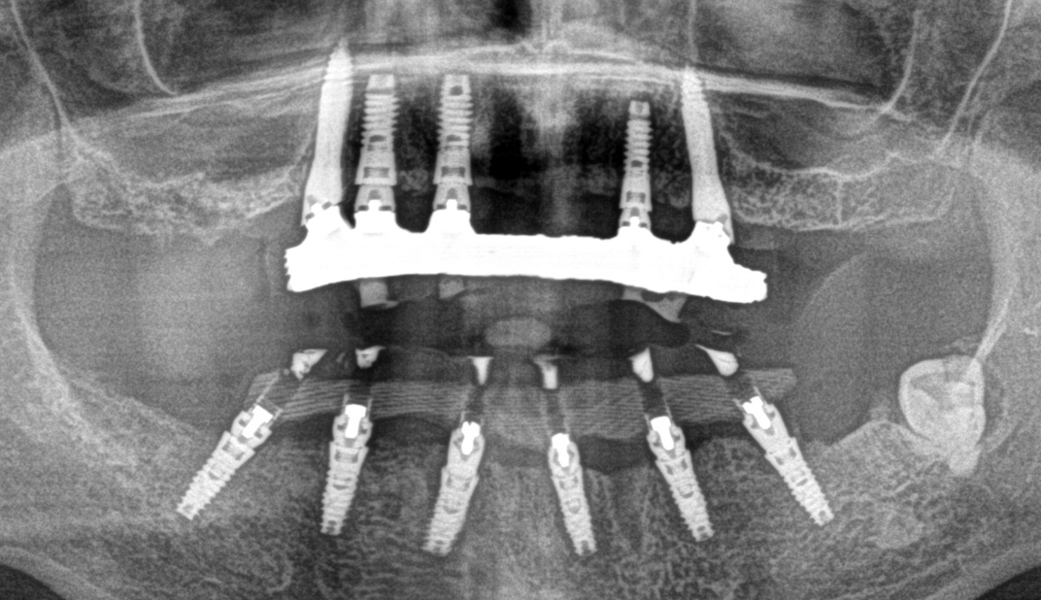

Fig. 1 : Bridges de transition CR/CO coulé/résine vissés en MCI.

Nous avons depuis la fin des années 1980 réalisé des prothèses avec succès en mise en fonction immediate après extractions et implantations. Celles-ci consistaient en une armature en CrCo coulée, sur laquelle étaient montées des dents du commerce, polymérisée en moufle de laboratoire. La rigidité de la contention était donc assurée, et la passivité de la structure obtenue par le collage de cylindres en titane dans l’armature, compensant ainsi les menues imperfections combines de l’empreinte, de la coulée du plâtre et de celle du métal (Fig. 1).